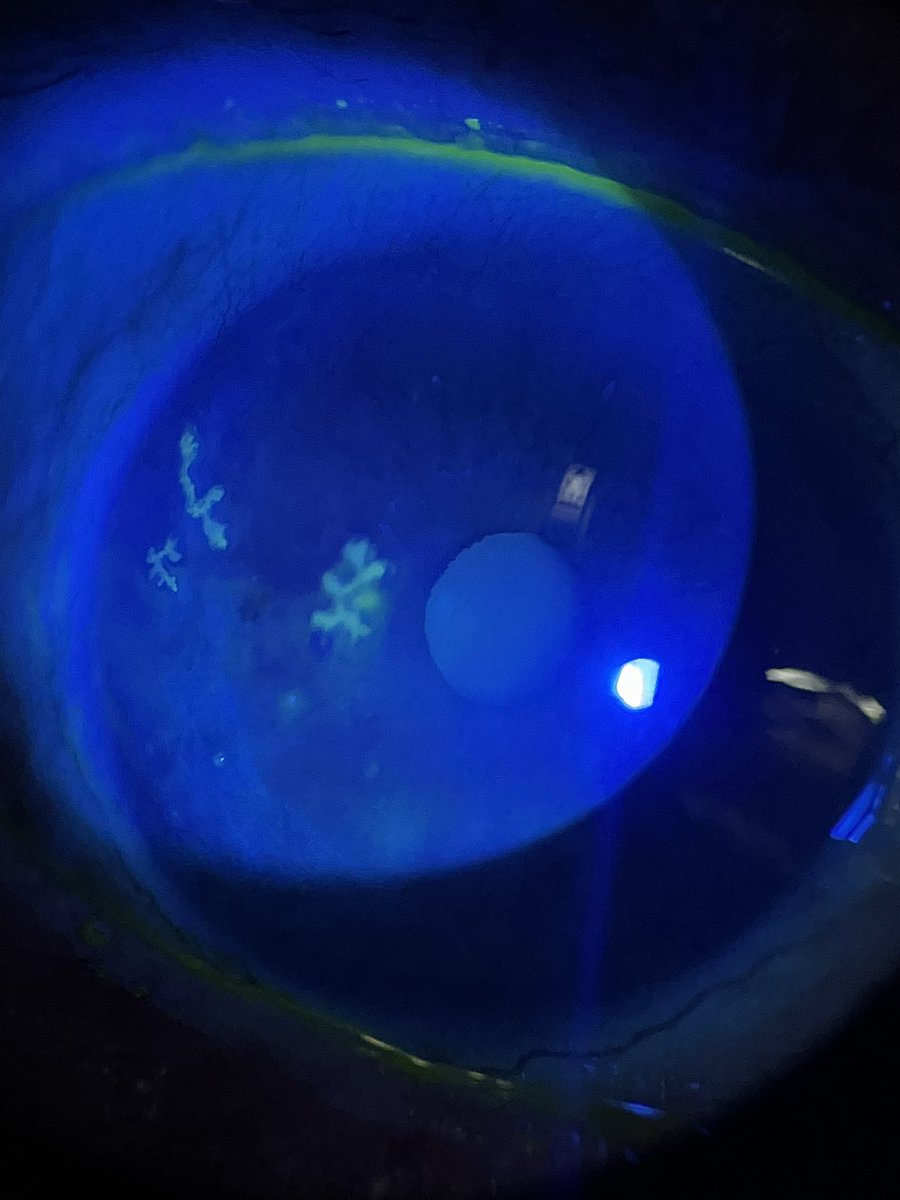

Eye MD | Fixing Eyes in Kashmir ❤️ | Cataract & Retina

🔗 Take the quiz: forms.gle/9DnrCQszG2BzhC… 📢 Clinical Ophthalmology MCQ Self-Assessment now live with answers & explanations across all subspecialties. Designed for postgraduates & residents preparing for IMM/Final fellowship exams. Mazhry-The Poet Ophthalmologist -ماہرِ چشم سخنور Acuity Eye Centre- The care your eyes need! Dr Hammad Nasti